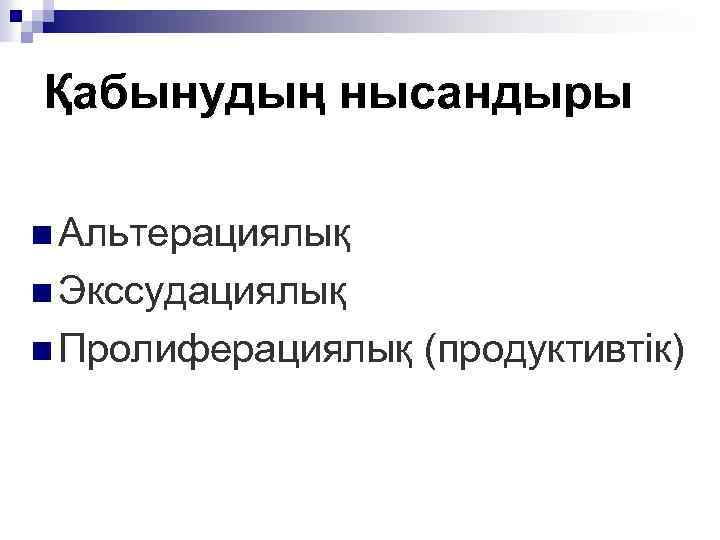

Қабынудың нысандыры n Альтерациялық n Экссудациялық n Пролиферациялық (продуктивтік)